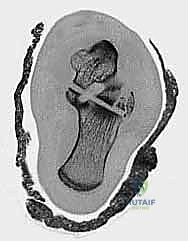

3. التصوير المقطعي المحوسب (CT Scan) - المعيار الذهبي

في عيادة الأستاذ الدكتور محمد هطيف، يُعتبر التصوير المقطعي المحوسب ثلاثي الأبعاد (3D CT Scan) إجراءً روتينياً وحتمياً لأي كسر في عظم الكاحل. توفر الأشعة المقطعية تفاصيل دقيقة للغاية عن خطوط الكسر، مدى التفتت (Comminution)، وحجم الإزاحة المفصلية التي لا يمكن رؤيتها بالأشعة السينية العادية. بناءً على هذه الصور، يقوم الدكتور هطيف ببناء استراتيجية الجراحة (أين سيفتح، ما نوع الشرائح والمسامير التي سيستخدمها، وكيف سيعيد بناء العظم).